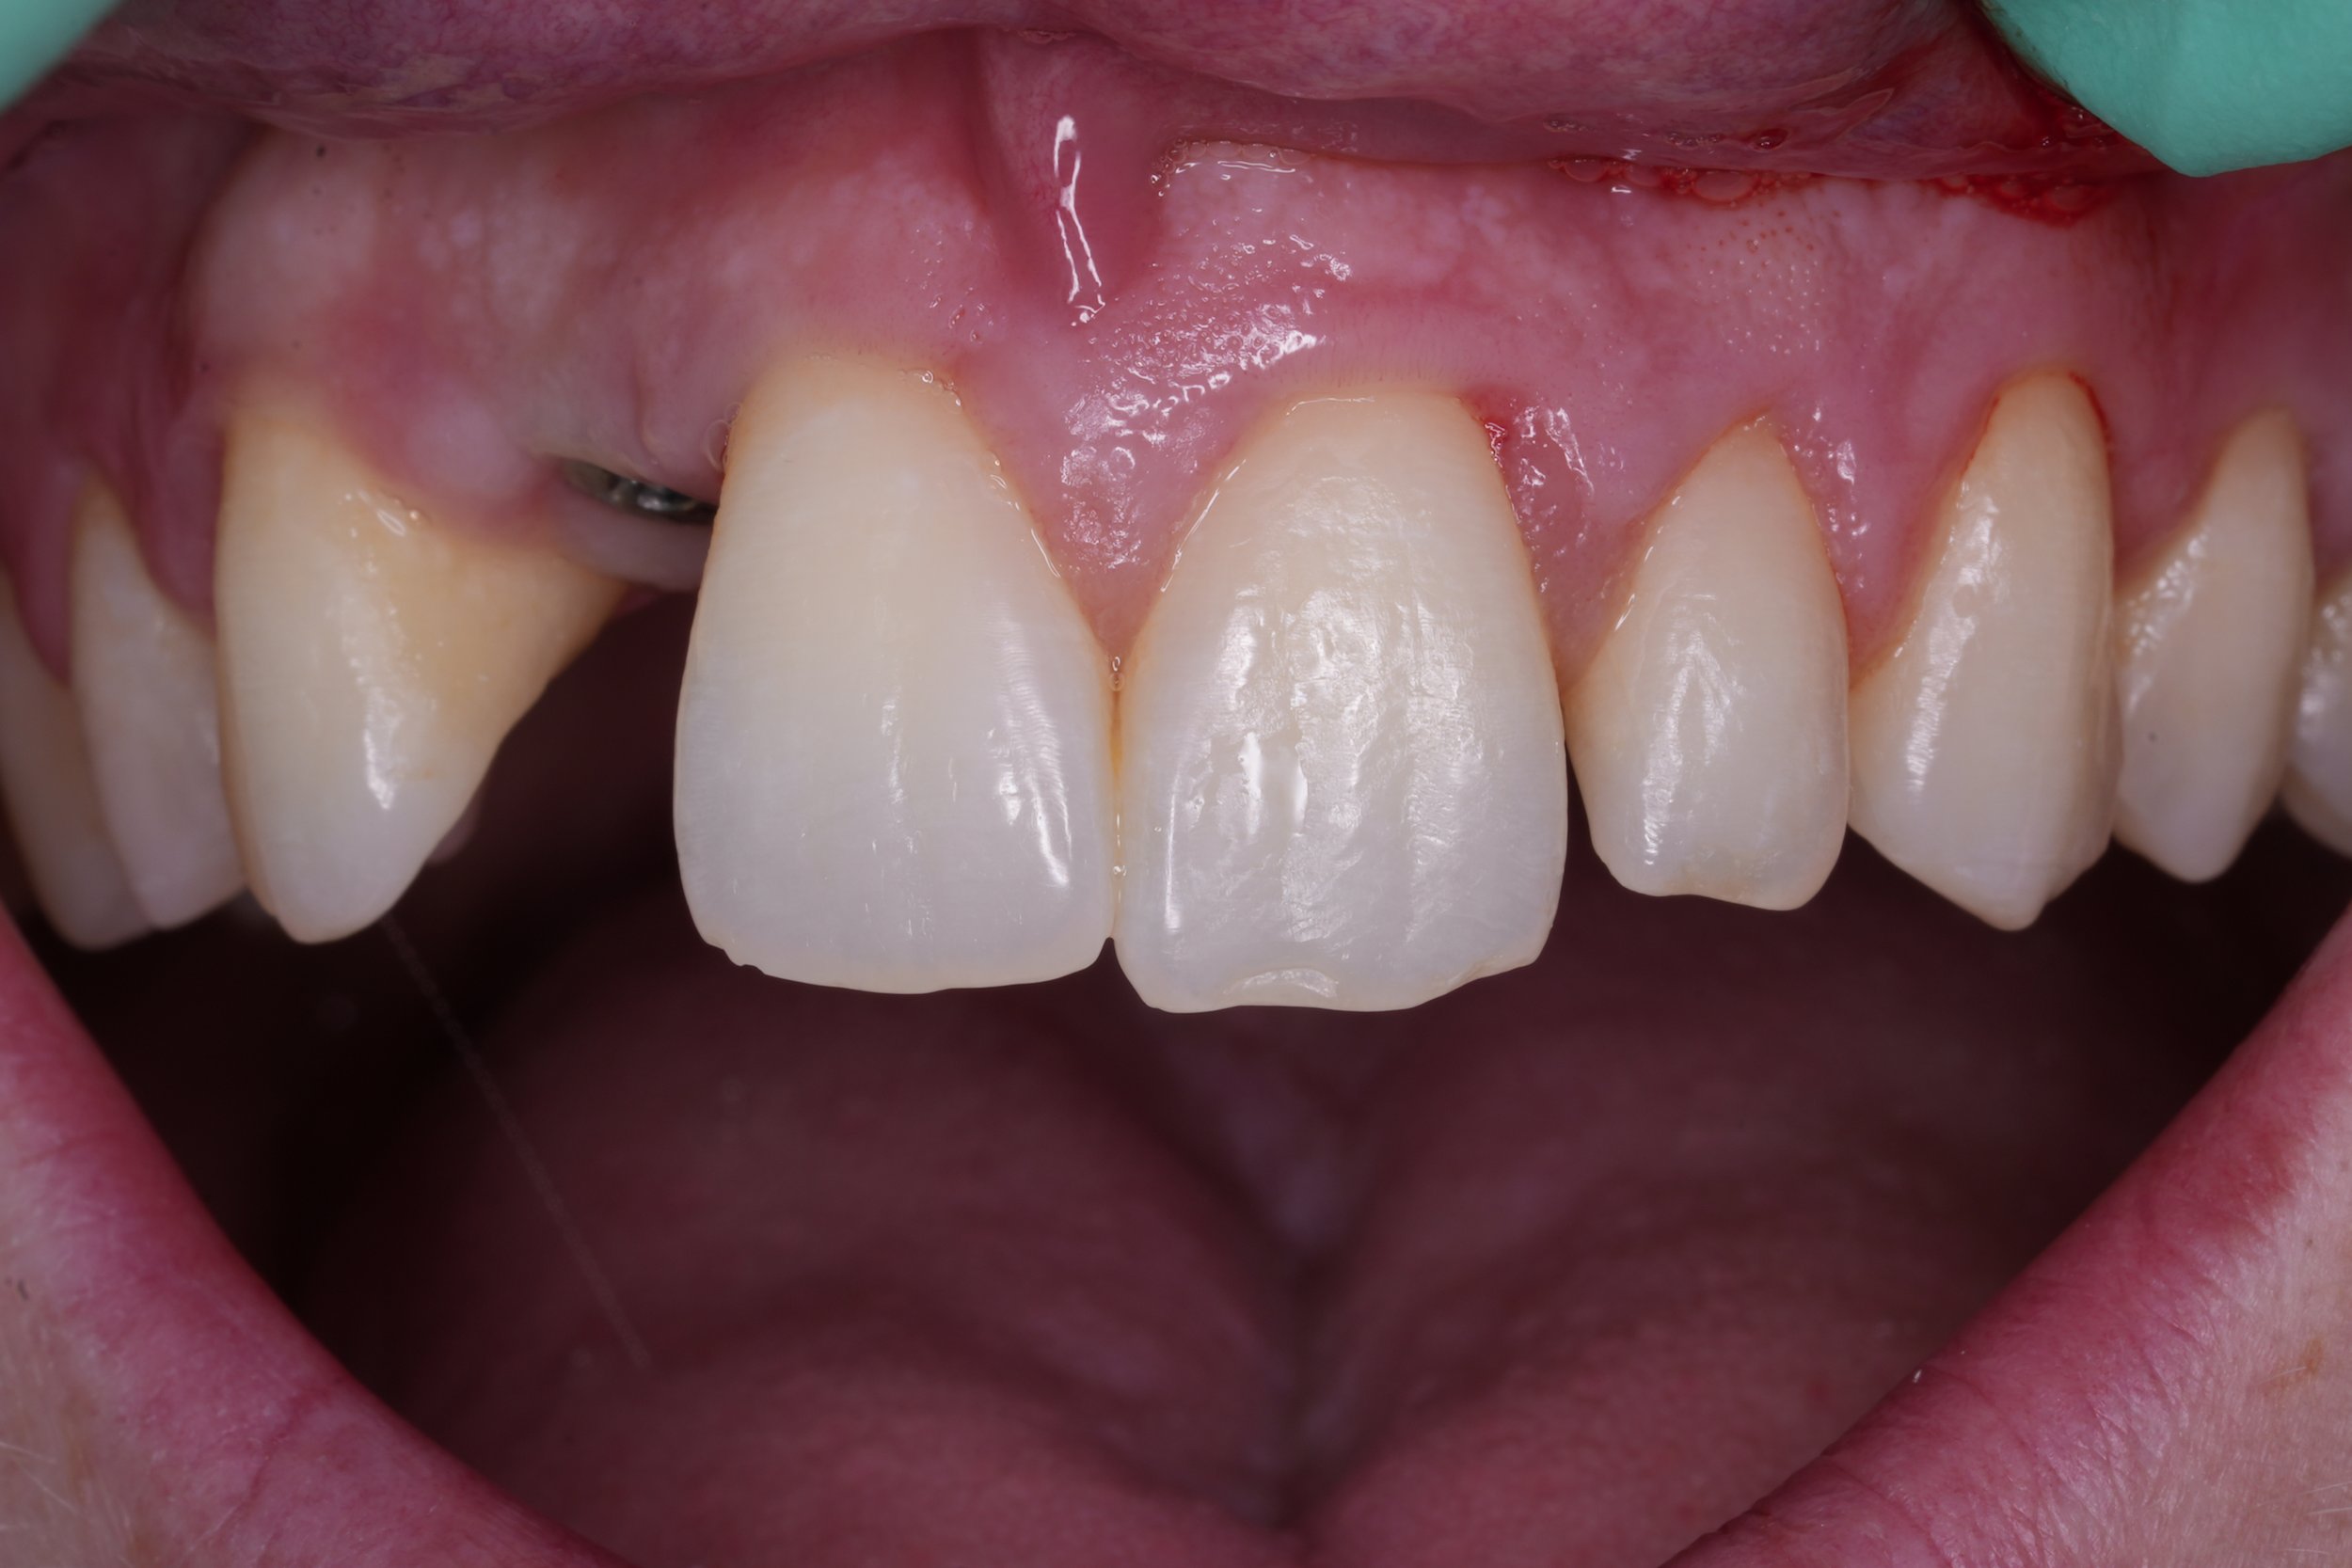

Fixed pros

Dental Implants